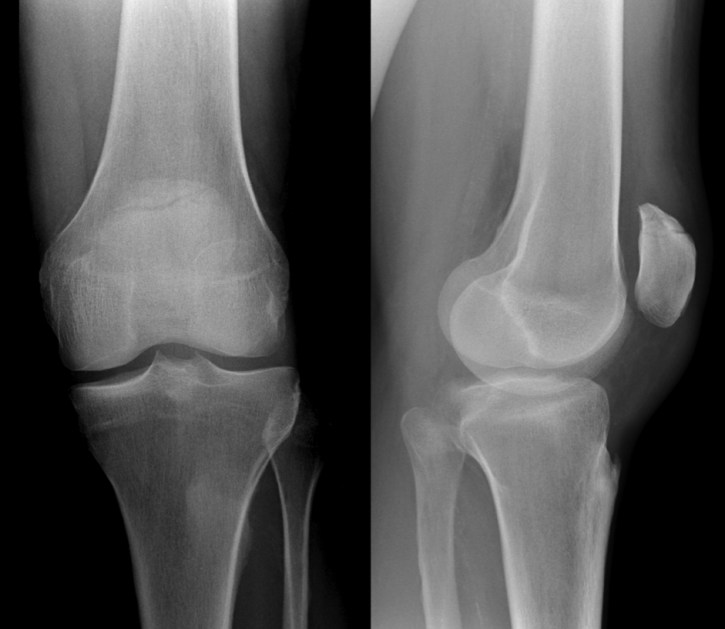

对于无移位骨折(移位小于2毫米),可采用保守治疗(图2)。Braun等与Böstman等提出,粉碎性骨折或髌骨上、下极骨折,只要符合上述前提条件,亦可采取保守治疗。但需注意,软骨或骨软骨骨折属于例外情况,即使其移位程度符合保守治疗标准,仍应实施手术复位固定。

图2:髌骨无移位骨折